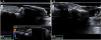

El estudio ecográfico, con sonda lineal multifrecuencia 9-14MHz y equipo de alta resolución (GE Medical Systems, Wisconsin, EE. UU.), puso de manifiesto dos LU superpuestas y un espacio hipoecoico entre ellas, disminución de la distancia entre el origen de la LU y la base de la falange distal, a nivel de articulación interfalángica distal, así como sombra acústica posterior bajo la LU de localización profunda. La medición del grosor del PUP resultó ser superior en la uña afecta que en la normal contralateral. Se observó un ligero incremento de señal doppler en la parte proximal del lecho ungueal, coincidiendo con el origen de la matriz (figs. 2 y 3).

A) y B) Comparativa ecográfica entre imágenes de los dos primeros dedos de pies, en el afecto de retroniquia A) se objetiva disminución de la distancia entre el origen de la lámina ungueal y la base de la falange distal, a nivel de articulación interfalángica distal. C) Incremento de señal doppler en la parte proximal del lecho ungueal.

El diagnóstico de la retroniquia es clínico, si bien la ecografía puede consolidarse como la prueba no invasiva de confirmación y para diagnóstico diferencial prequirúrgico. Los criterios ecográficos en los que se sustenta son: presencia de dos o más LU superpuestas, disminución de la distancia entre el origen de la LU y la base de la falange distal, a nivel de articulación interfalángica distal, reflejo del desplazamiento posterior de la uña; así como una disminución de la ecogenicidad en dermis del PUP y en la parte proximal del lecho ungueal, por la presencia de inflamación y onicólisis7,8. En el paciente presentado se observó además, ausencia de ecos bajo la LU de localización más profunda, que se atribuyó a sombra acústica posterior. El estudio doppler ha demostrado en un caso, un leve incremento del flujo sanguíneo en el lecho ungueal proximal7.